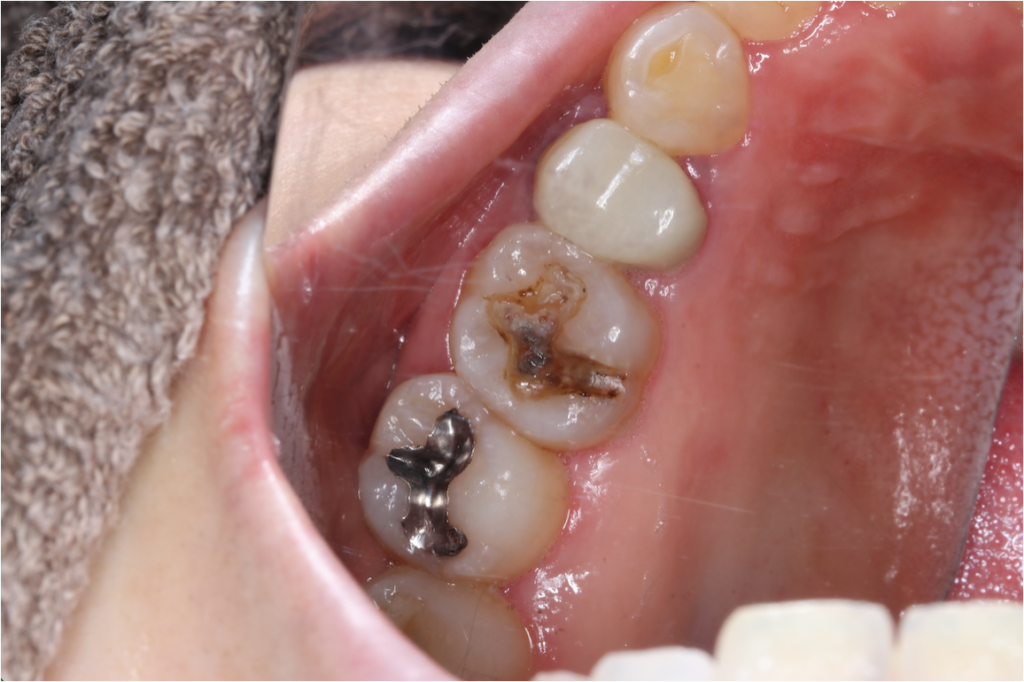

セラミック症例②

年齢 40代女性

治療期間 1ヶ月

治療内容 ジルコニア

治療箇所 右上6番

治療費用 100,000円